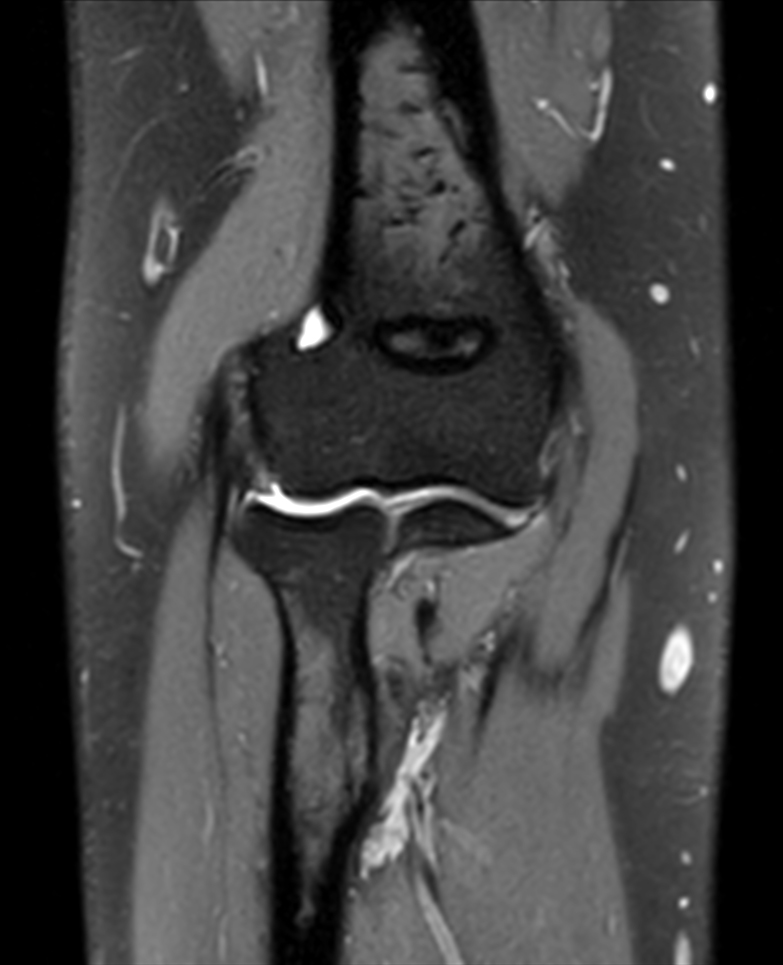

Large FOV imaging with the dS 16ch Small Extremity coil

Used Solution

• System

• Coil

• Clinical Application